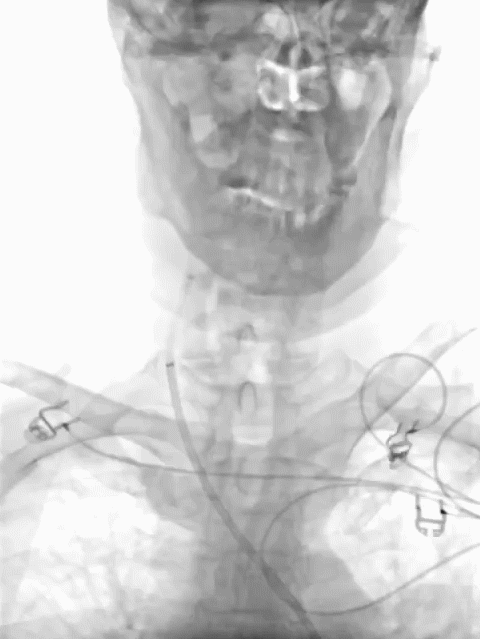

患者仰卧位,局部麻醉后,右侧腹股沟动脉穿刺插管,放置8F长鞘,将通桥大禹®球囊导引导管置于右侧颈内动脉,造影显示右侧大脑中动脉M2段闭塞,远端无显影。